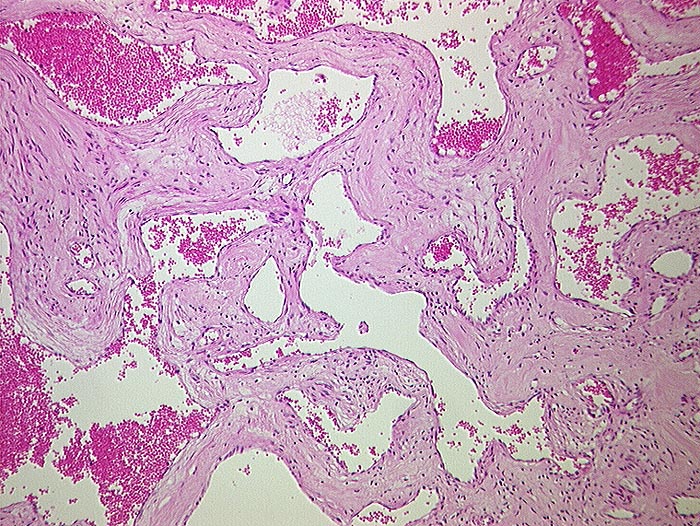

AP/ Hämangiom

Hämangiom

benigner Tumor

Leber, Gallenwege, Pankreas

Leber